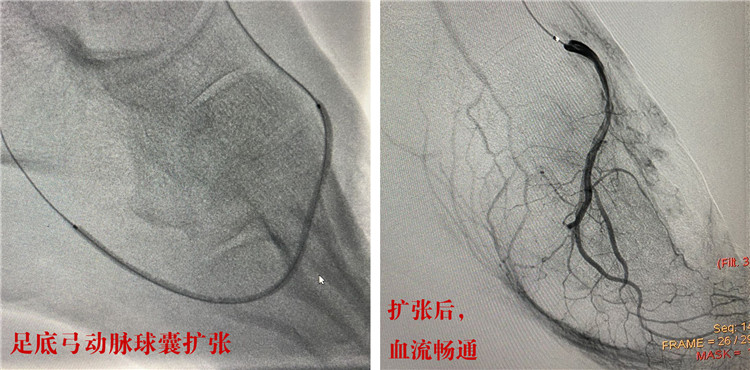

首先,由經(jīng)驗(yàn)豐富的放射科介入團(tuán)隊(duì)成功行下肢動(dòng)脈硬化血管球囊擴(kuò)張,血管開(kāi)通后,陳先生的左下肢血流立刻恢復(fù)暢通;隨后,燒傷科為陳先生切除了左腳的干性壞疽,并給予潰瘍清創(chuàng)及腳面植皮;內(nèi)分泌科全程監(jiān)控,幫助患者控制血糖的同時(shí),耐心換藥護(hù)理。